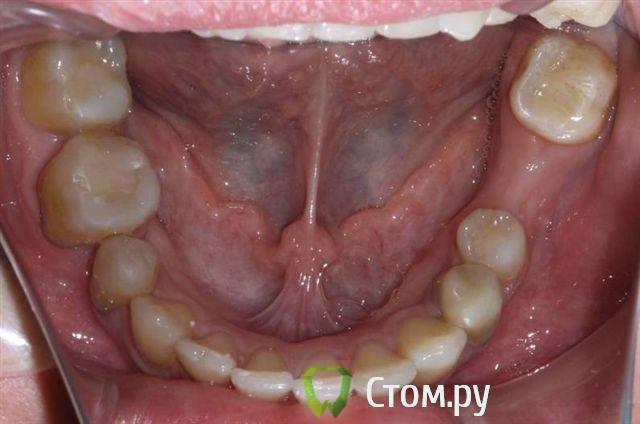

Александрстрад Опубликовано 8 ноября, 2011 Поделиться Опубликовано 8 ноября, 2011 Уважаемые доктора! Потерял и веру и надежду в возможность решения проблемы у своей жены. Одел на нее брекеты у знакомых ортодонтов в Москве, результаты, которых видел. В процессе лечения консультировался и ЦНИИСЕ у Арсениной и у других докторов, работал в крупнейшей медицинской компании, доступ к врачебной базе был очень большой. В процессе лечения все говорили что лечение идет нормально, а когда сняли брекеты ужаснулись все. Хронология лечения у ортодонта описана ниже, включая проблемы, которые мы получили после лечения.1. Показания к лечению брекет-системамиХруст при жевании в правом суставе.Замещение отсутствующего на нижней челюсти пятого зуба справа в течение 10 лет. В результате отсутствия 5-го зуба: наклон 4-го и 6-го по направлению друг к другу, резорбция (убыль) костной ткани на челюсти на месте отсутствующего зуба.Левый клык на верхней челюсти выходил из зубного ряда.Смешение центра верхней челюсти влево.Правый клык до момента начала лечения на верхней челюсти не вышел, находился в состоянии ретинированного, т.е. не вышел.2. Этапы леченияНачало лечения брекет системой - 2006 год.Снятие брекет системы 2009 год.Что было сделано:1. Левый клык на верхней челюсти был поставлен в зубной ряд.2. По отсутствующему 5-му зубу на нижней челюсти - доктор принял решение по замещению, путем передвижения зубов на нижней челюсти вправо,что и было проделано.3. Через 2 года ношения брекет-системы было принято решение по вытаскиванию левого ретинированного клыка.Был удален 3-ий зуб и в освободившееся пространство был вытянут клык.В результате данного объема работ и некорректной работы доктора,были завалены внутрь зубы на верхней челюсти - левая сторона, начиная от 1-го и далее, от резцов до жевательных.Также после сделанного панорамного снимка выяснилось, что произошло рассасывание корней 4-х фронтальных зубов на верхней челюсти более 65%.4. Также в процессе лечения был потерян 6-ой зуб на нижней челюсти слева. Проблемы сейчас1. Хруст в челюсти при жевании и зевании не прекратился, а появился и слева.2. Заваленная левая часть зубов на верхней челюсти не позволяет смещать нижнюю челюсть влево,тем самым перегружаются жевательные мышцы справа, в результате бывают головные боли и боли в мышце при жевании.3. Рассасывание 4-х верхних зубов.4. Расстояние справа между верхней и нижней челюстью на данные момент 3 мм. Сделали после снятия бректов исселдование у ортопеда, заключение ниже. Ее приговор - ТОТАЛЬНОЕ протезирование.Жене 36 лет, она даже слышать об этом не хочет. ПОМОГИТЕ РЕШИТЬ ПРОБЛЕМУ, НАДЕЖДЫ БОЛЬШЕ НЕТ. Заключение ОРТОПЕДАTreatment objectives∙ Transversal and sagittal discrepancy- make passive centic arch of upper jaw fit to active centric active lower jaw∙ First interference contact in RP on 24-34 and 37-27 with disocclusion for + 2 mm. Rp= 0=-2 mm, and till last contact =-4mm on incisal pin, so increase IP for =+3mm∙ Muscle problems∙ Change OPI on right side from 15 degrees to 20 degreees and change Cui right side to∙ Increse LFH +3 mm on incisal pin∙ Curve of Spee will be accentuated for 36∙ Steep condyle- decreased radius curve of Spee∙ Cui for 13 is not more than 55 degrees∙ Curve of Spee=Curve of wilson for 36 and 46∙ Rotation of mesial cusp of 6 down- change OPI for 36 – rotate 36 with mesial contact point OPI 6 = 35 degrees for DOA=12 degrees Ссылка на комментарий